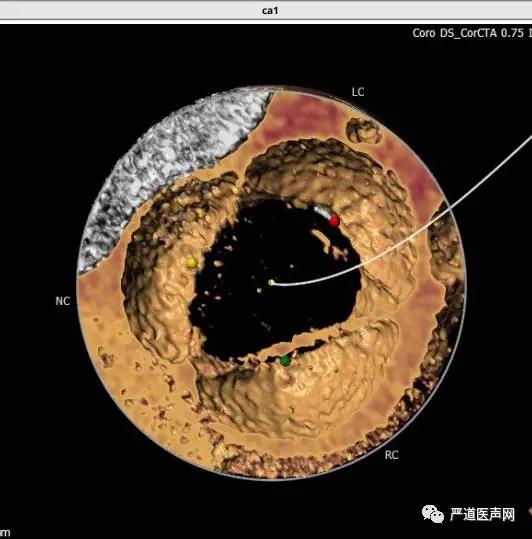

经CT评估:

· 患者主动脉瓣三叶式,瓣叶基本等大,瓣膜无明显增厚和钙化。

· 患者主动脉瓣环周长折算直径31.72mm。

· 患者左室流出道环下4mm直径33.2mm,环下6mm直径36.2mm。